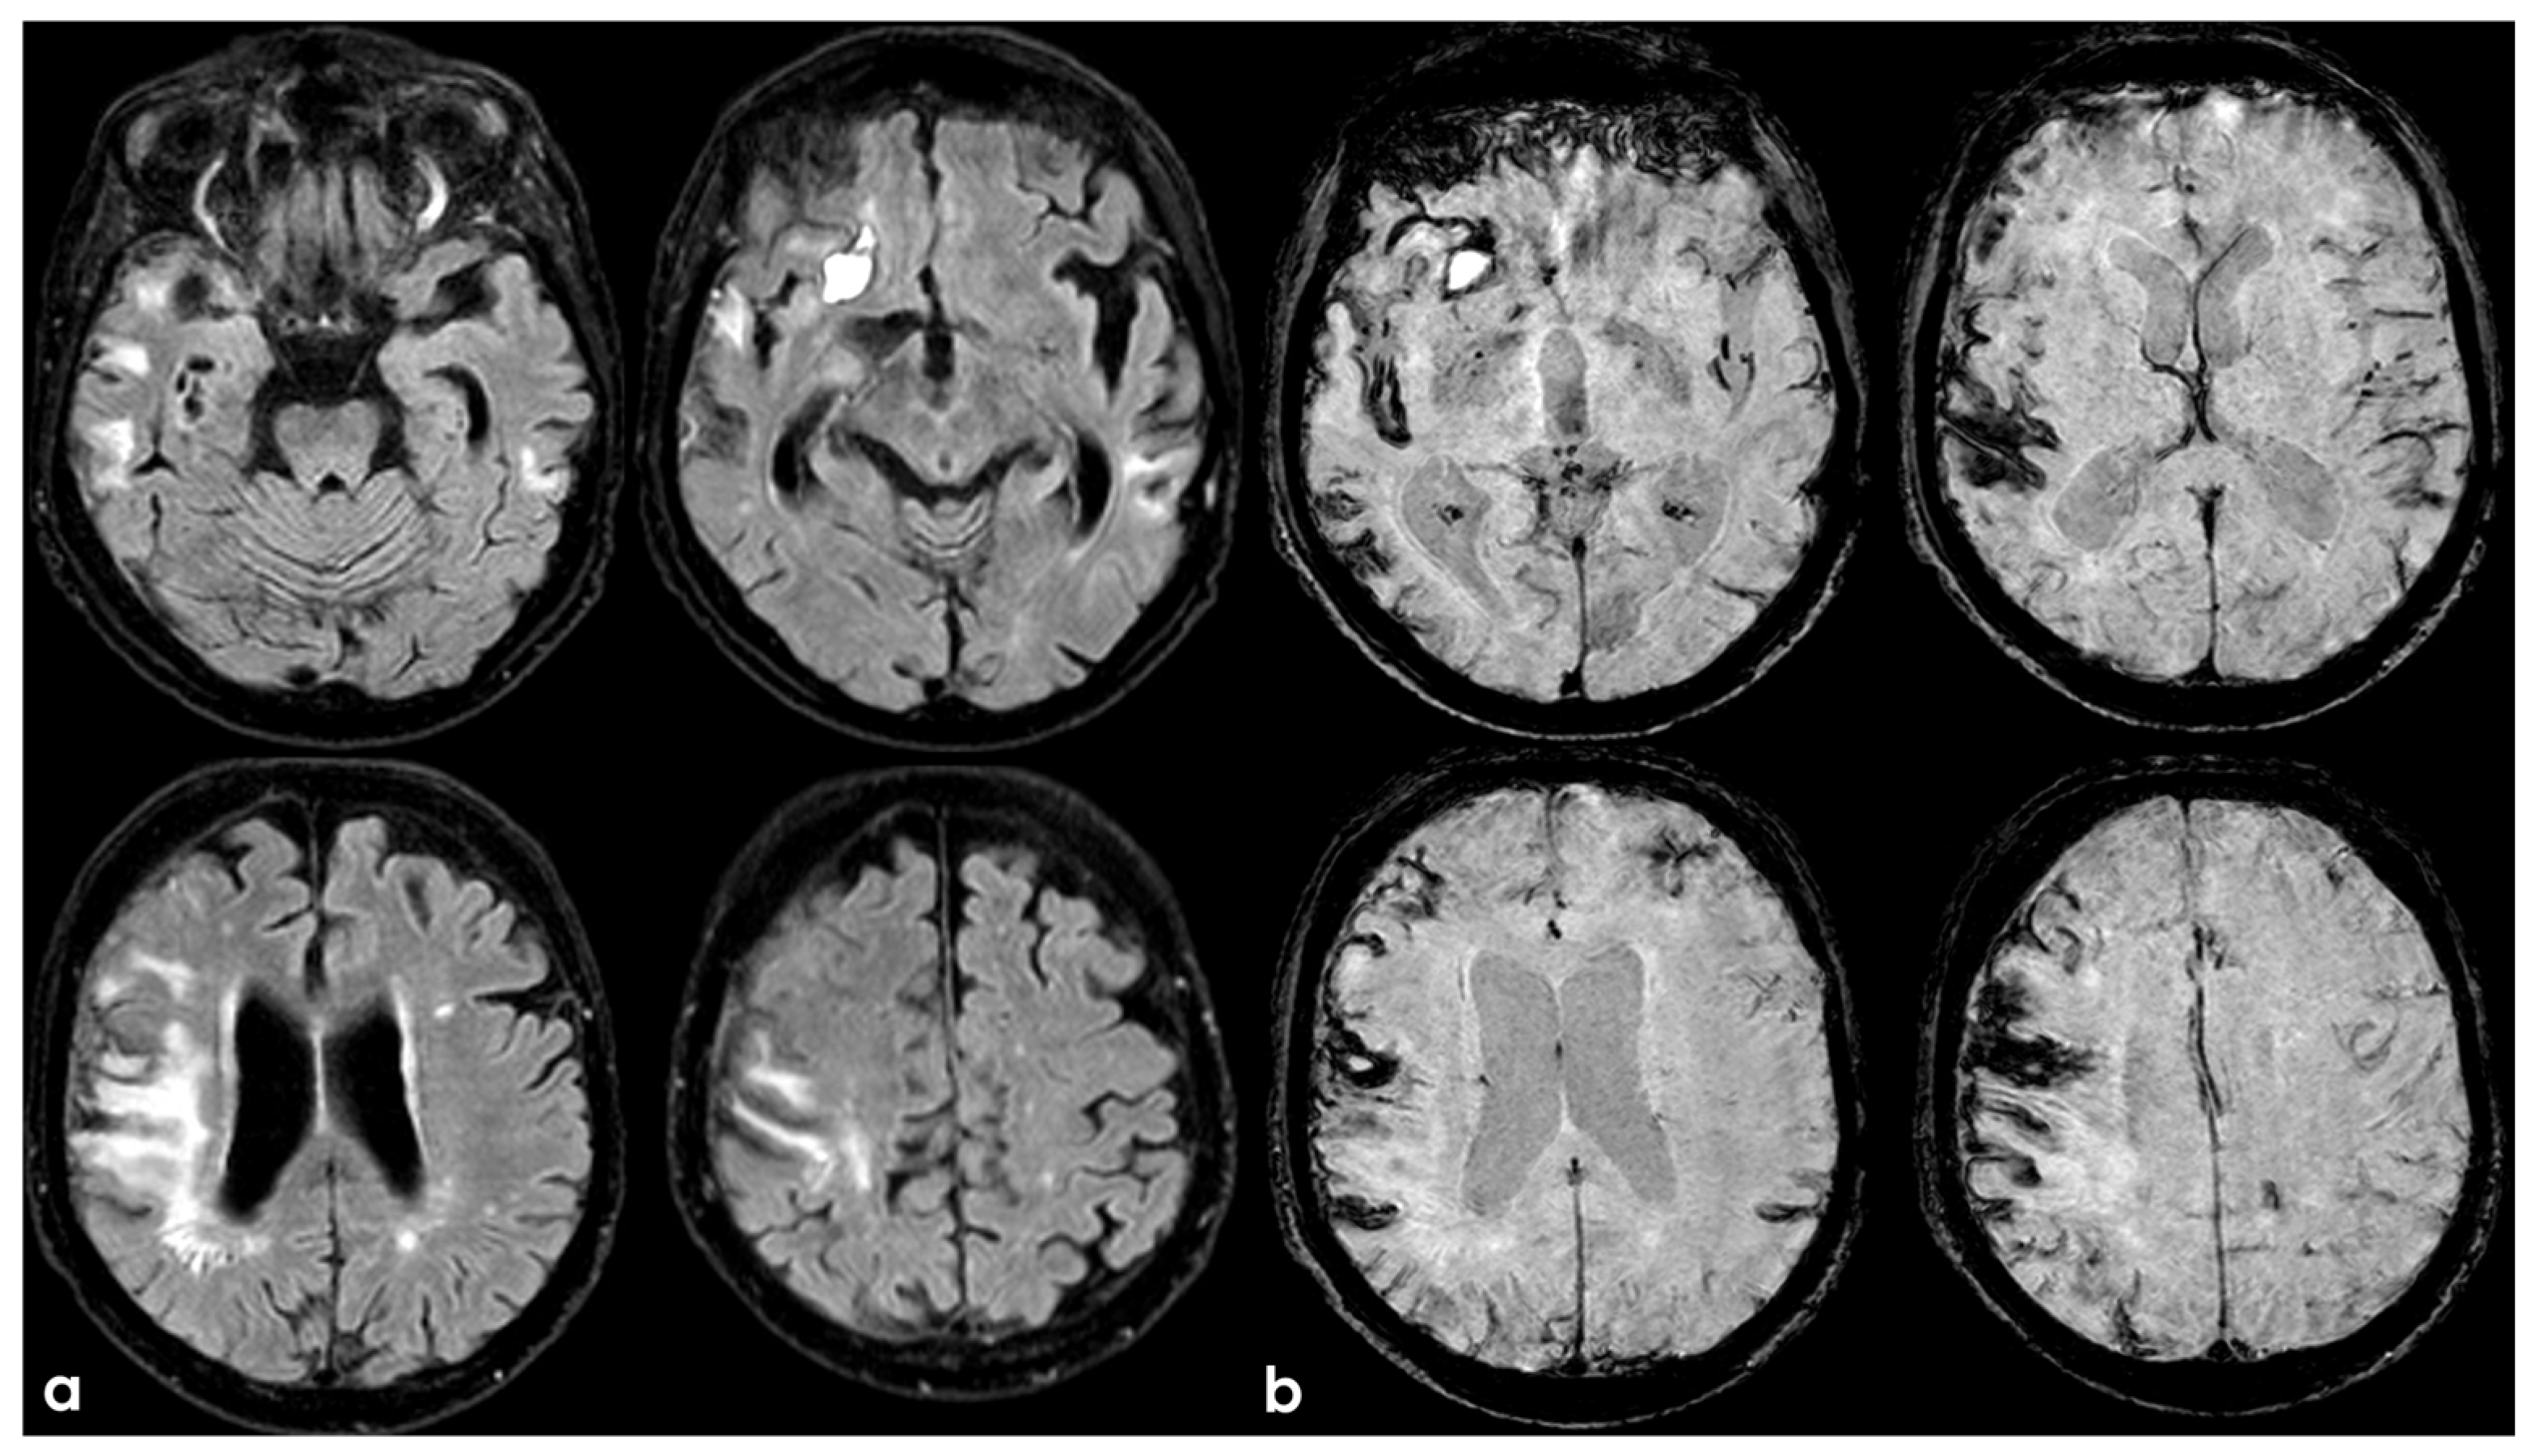

7. Structural Neuroimaging Markers